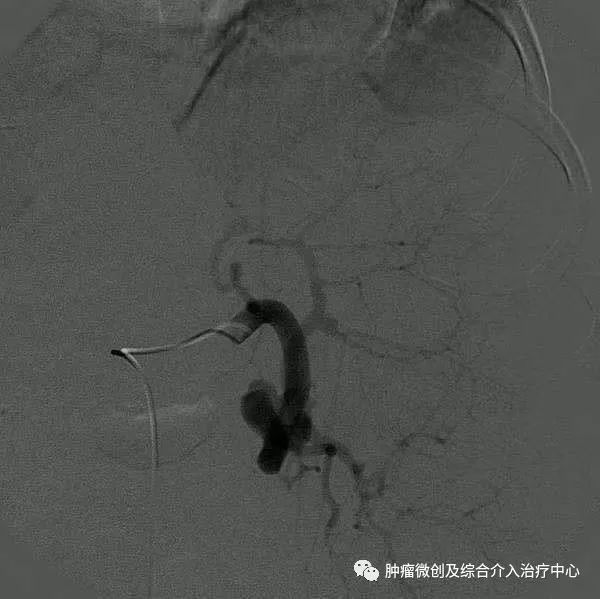

1.采用Seldinger技术经股动脉或肱动脉穿刺插管行腹腔动脉造影,以每秒8ml,总量15~20ml注入造影剂,观察脾动脉走行。

2.借助导丝将导管超选至脾动脉造影,以每秒5~8ml,总量15~30ml注入造影剂,观察脾脏的大小及脾内病变情况,脾破裂可见造影剂外渗、血管离断等影像改变。

3.根据脾脏病变及不同的栓塞方法选择栓塞材料。部分脾动脉栓塞多采用明胶海绵颗粒,约2mm3,浸入含青霉素和庆大霉霉素的生理盐水中;也有主张用明胶海绵短条,约2mm×8mm大小,插入2ml注射器乳头中注入,一般为6~8条。栓塞时导管尽量超选至深处,最好越过胰背动脉,以防误栓造成医源性胰腺炎。术中通常根据脾动脉的血流来判断脾脏栓塞程度,笔者的经验是脾动脉血流稍减慢栓塞范围为30%~40%,明显减慢为50%~60%,若短暂停流后呈蠕动前进为70%~80%。全脾栓塞时多采用明胶海绵粉末或无水乙醇,导管超选应更为准确、深入,必要时可通过3F微导管或球囊导管注入无水乙醇等液态栓塞剂,以免反流。脾动脉主干栓塞时多选用不锈钢螺圈,栓子直径应略大于脾动脉管径,导管置于脾动脉近端,但仍应越过胰背动脉开口。

4.再次脾动脉造影,明确脾栓塞程度。若感不足,可补加栓塞,直至满意为止。退出导管,穿刺处压迫止血后加压包扎,平卧24h。